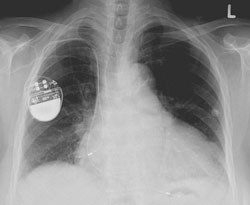

محققان حوزه امنیت، از احتمال نفوذ هکرها به دستگاههای ضربانساز قلب (پیس میکر)، بازنویسی برنامه اولیه، آلوده کردن آنها با کدهای مرگبار برای ایجاد شوک یا حتی خاموش کردن دستگاه هشدار میدهند.

این کارشناس با استفاده از یک لپ تاپ، مجموعهای از شوکهای الکتریکی با ولتاژ 830 ولت را از راه دور به یک ضربانساز ارسال کرده و با استفاده از «عملکردهای مخفی» نامشخص میتوانست تمامی دستگاههای ضربانساز (pacemaker) و ایمپلنتهای انقباضدهنده قلبی داخلی (defibrillator) را در شعاع 9.1 متری فعال کند.

بدترین سناریوی مطرح در این زمینه، احتمال بروز این خطر برای صد درصد دستگاههای ایمپلنت قلبی است که با ایجاد شوکهای ناگهانی یا خاموش شدن دستگاه میتواند منجر به مرگ بیمار شود.